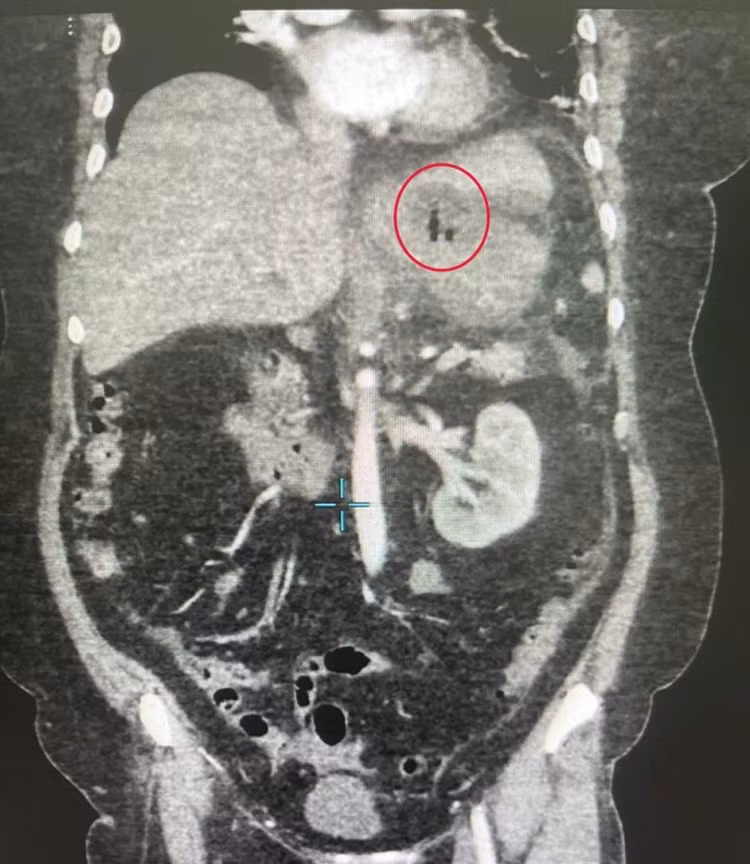

Hình ảnh cận lâm sàng cho thấy xương cá trong dạ dày - Ảnh BVCC

Sau hội chẩn khẩn giữa các bác sĩ khoa Ngoại Tổng quát và ê-kíp trực cấp cứu, bệnh nhân được chỉ định mổ cấp cứu. Ban đầu, các bác sĩ định thực hiện phẫu thuật nội soi. Tuy nhiên, do tổn thương nằm sâu, giả mạc bao quanh, dịch mủ đặc và nhiều dính, phẫu thuật nội soi gặp khó khăn nên phải mổ hở.

Ca mổ được thực hiện bởi các bác sĩ khoa Ngoại tổng quát, với sự dẫn dắt của BS.CKII Lê Tòng Bá, Phó Trưởng khoa. Qua đường mổ dài khoảng 15cm trên rốn, các bác sĩ phát hiện một ổ áp xe lớn phía mặt sau bờ cong nhỏ dạ dày, chứa nhiều mủ trắng đục.

Khi bóc tách ổ áp xe, các bác sĩ đã phát hiện một chiếc xương cá dài khoảng 4cm đâm xuyên qua thành dạ dày. Đây chính là “thủ phạm” gây thủng và tạo ổ mủ kéo dài suốt thời gian qua.